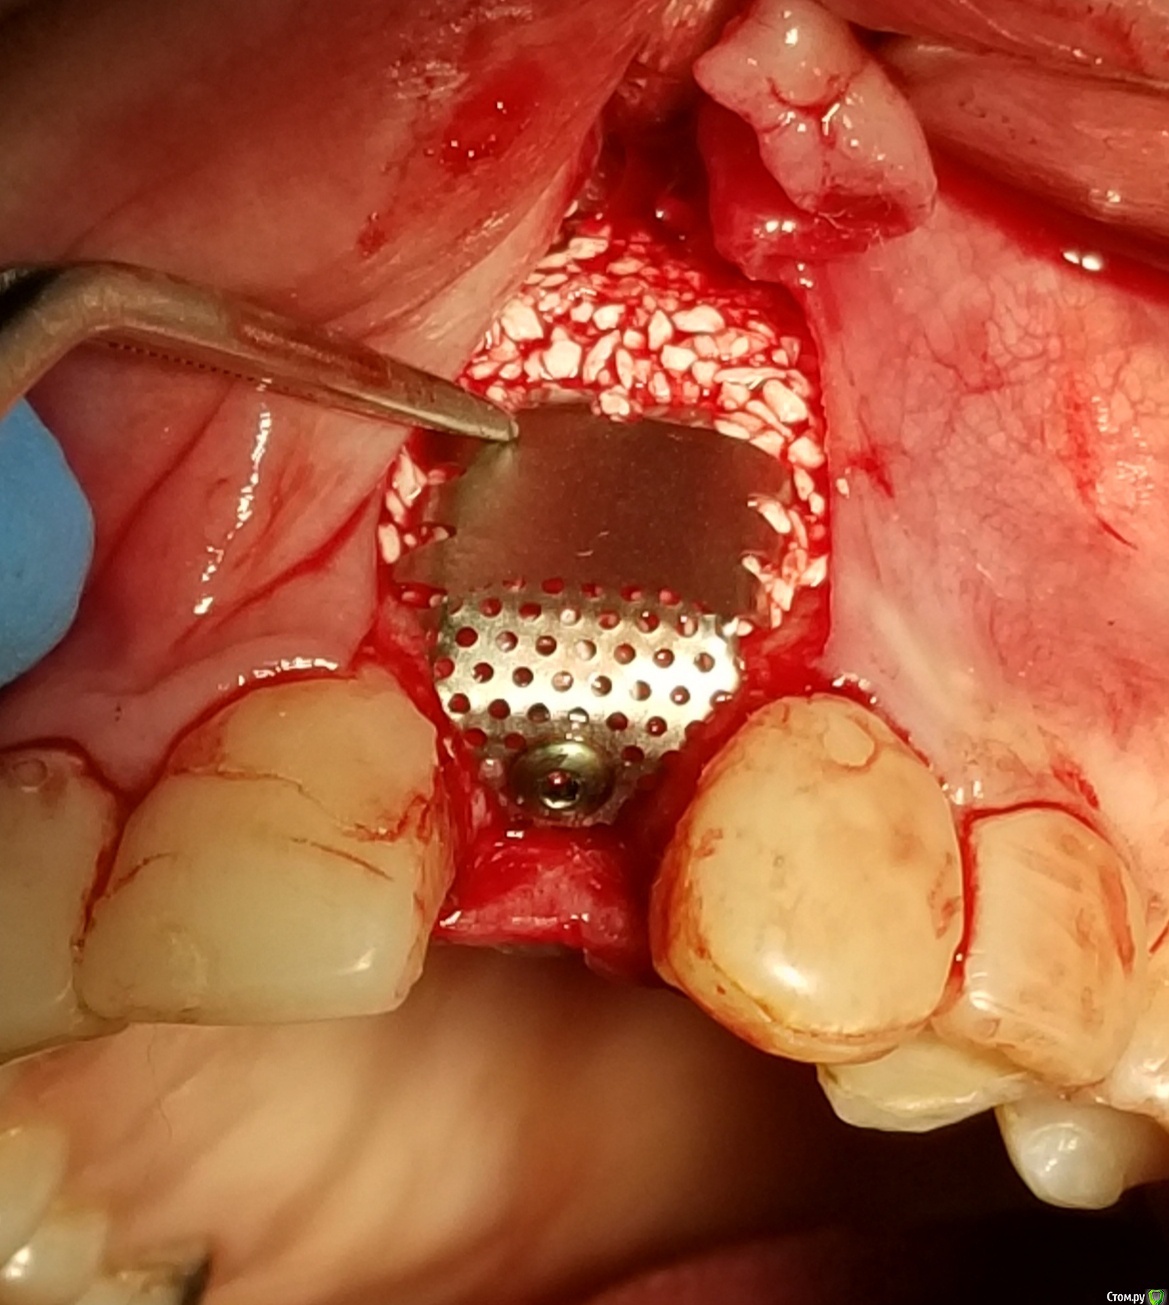

Kostoprav Опубликовано 18 сентября, 2018 Поделиться Опубликовано 18 сентября, 2018 Апатос+ ПРФ+ инъекционный ПРФ+ титановая мембрана.кт через 4,5 мес.Честно говоря кости ожидал побольше, так как паковал с гиперобобьемом. Ссылка на комментарий

АнтонТЛТ Опубликовано 18 сентября, 2018 Поделиться Опубликовано 18 сентября, 2018 У шейки недопаковано было, апикальной лучше фиксировать, вертикальные разрезы надо не так делать. Спейсер неродной что ли? 6 Ссылка на комментарий

stommm Опубликовано 20 сентября, 2018 Поделиться Опубликовано 20 сентября, 2018 Имхо для такого дефекта лучше сетку подлиннее (у нео есть такие) что бы апекально фиксировать в кости, а не так что апекальный край сетки лежит над дефектом. И Имплант по фото недогазлублен. Либо профиль неудачный будет, либо коронка короткая. При бОльшем заглублении имхо получилось бы лучше Ссылка на комментарий

Kostoprav Опубликовано 20 сентября, 2018 Автор Поделиться Опубликовано 20 сентября, 2018 Имхо для такого дефекта лучше сетку подлиннее (у нео есть такие) что бы апекально фиксировать в кости, а не так что апекальный край сетки лежит над дефектом. И Имплант по фото недогазлублен. Либо профиль неудачный будет, либо коронка короткая. При бОльшем заглублении имхо получилось бы лучше имплант с полированой шейкой, эго не желательно сильно погружать под кость.В инструкциях производителя этот тип мембран не предназначен для апекальной фиксации, есть мембраны с проререзями под винты но у нас таких не продают. Ссылка на комментарий

АнтонТЛТ Опубликовано 20 сентября, 2018 Поделиться Опубликовано 20 сентября, 2018 имплант с полированой шейкой, эго не желательно сильно погружать под кость.В инструкциях производителя этот тип мембран не предназначен для апекальной фиксации, есть мембраны с проререзями под винты но у нас таких не продают.Только шейка не полированная, а фрезерованная. Мембраны с прорезями это более новый вид. Мембраны без прорезей можно пробивать пином или пин/винт крепить между ножек. В вашем случае, если не прибивать, то надо было мембрану лучше загнуть или взять больший размер, чтобы мембрана опиралась на кость апикально. 2 Ссылка на комментарий